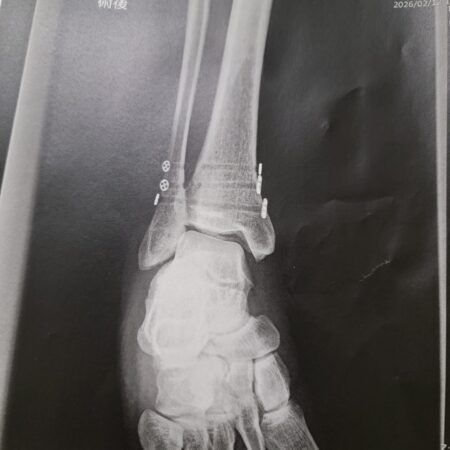

Hokkaido Ski Accident (Part 3): The surgery pain-cave

Hokkaido Ski Accident (Part 2): Meeting Dr. Tsujino

Hokkaido Ski Accident (Part 1): Breaking a bone and tearing ligaments